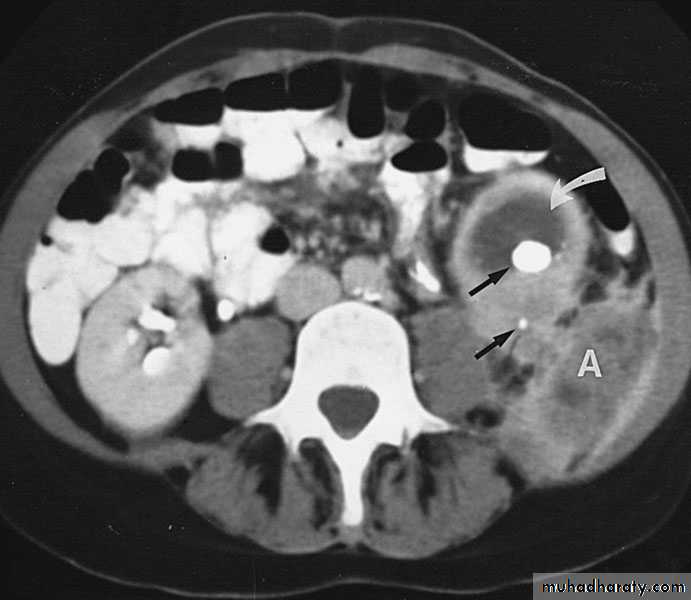

Renal Abscess or Renal Carbuncle

Renal abscess or carbuncle is a collection of purulent material confined to the renal parenchyma.The renal parenchyma contains an encapsulated necrotic mass

Insidious onset (may run > 2 weeks)

Obscure fever

Local pain

Symptoms of the primary cause

Tender renal angle

Tender mass : differentiate from malignant lesion

Bacteriology

Hematogenic infection

Commonly coliforms & staph aureous, proteous, klebsiella.

Predisposing factors

Diabetic patientsI.V drug therapy

Hemodialysis

Immunocompromized

Skin infection

Rarely ascending infection

Clinical picture

Usually underlying pathology:systemic bacterial infection, skin infections, urinary stones, vesicoureteric reflux, obstruction, DM

Infection—liquefaction—abscess formation

Male : female 3:1

Age : 20---30 year

Loin Pain

Fever

On exam.: renal angle tenderness

Investigations

U/S

KUB, IVU

CT scan

Treatment

Medical: RestAnalgesia

Antibiotics

Follow up examination

Surgical: Abscess drainage

Nephrectomy